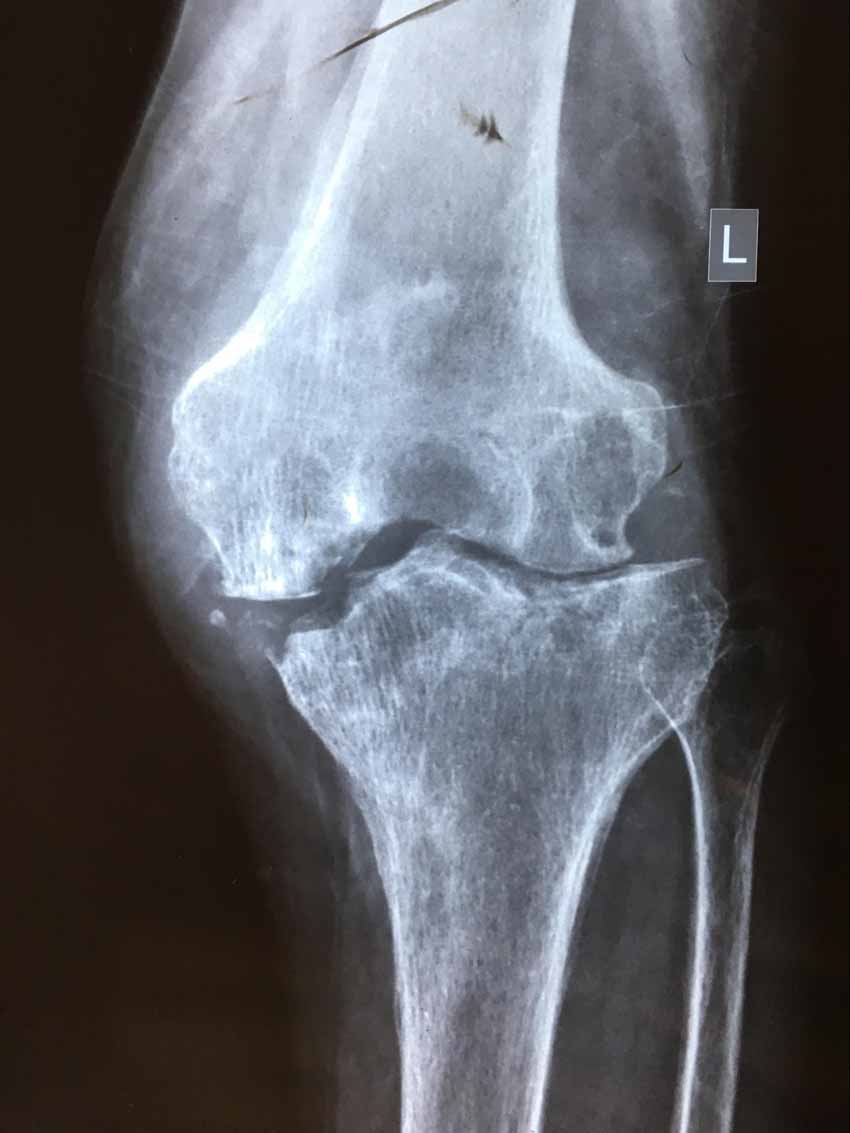

In my third week I had a 71 year old female come to the clinic, a trip that took her nearly five hours with the assistance of her son and daughter-in-law. Her chief complaint was excruciating left knee pain, which was about the size of a small melon. After reviewing her x-rays and doing a knee exam, it was very clear to me, even with no background in radiology, that this woman's knee was totally overcome with osteoarthritis, almost non-existent cartilage, and ligaments like noodles. The only thing that would help her walk again would be knee replacement surgery. In most developed nations this is doable. For people scratching out a living in rural Nepal, this is a very limited to near impossible option. She looked at me point blank and asked in Nepali without even looking at my interpreter and said "Can acupuncture fix this? Can you get me to walk again?" and with a huge lump in my throat I replied, "No. Acupuncture can't help this." It was an extremely humbling moment considering how much effort she had gone through to get to the clinic. This pushed me to extend myself and explored what options were available and what I could actually do to help this patient.